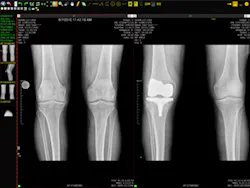

IMAGE COURTESY VIZTEK